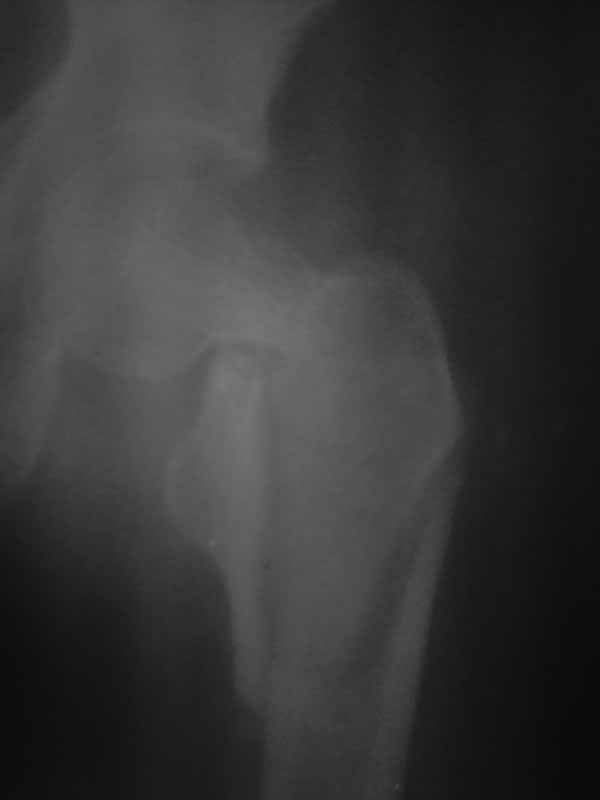

Доброго времени суток уважаемые коллеги!! Если бы перелом был чрезвертельным то все примерно было бы понятно. Гамму пациентка не купит, больница тоже ее не купит. Я попытался прислать еще снимки гляньте пожалуйста. Можетбыть вести действительно консервативно чтобы прирос фрагмент межвертельного перелома а потом поднять речь об эндопротезировании, ища квоты?! DXS - я говорю об динамическом бедренном винте с накладкой. Единственно что есть это LSP пластины да в шейку загнать винты АО. А больница наша скоропомощная в г.-герое Москва №68. Спасибо всем ответившим и прочитавшим. Случай не простой.

Нет КТ - качественный Рн нужен. Консервативное лечение здесь не рассматривается, как однозначно калечащее. Видно - нужно быть готовым к открытой репозиции. Винты не обеспечивают достаточной стабильности при такой линии излома. И, даже если бы была возможность ИМ фиксации, я бы предпочёл Динамический Бедренный Винт (так правильно?) в этом случае. Черкните мне, или позвоните, если нужна поддержка, приеду, помогу по соседски-то. Вы же в Коньково? Андрей

Этот случай не является типичным, я бы рассматривал его с точки зрения механики как комбинацию (редкую, надо сказать, комбинацию) латерального и медиального переломов. Если я правильно могу прочитать представленные рентгенограммы, конечно. И нестабильным как раз в данном случае является медиальный компонент повреждения. Поэтому выбор технологии диктуется медиальым, сложным компонентом. Для латерального по большому счёту всё равно - гвоздь или Динамический Бедренный Винт. Для базисцервикальной шейки же гвоздь не даёт особых преимуществ. Репозиция, скорее всего, будет октрытой. Поэтому, DHS в комбинации (если войдёт)с дополнительным антиротационным винтом. Но, -прежде всего, рентгенография нужна приемлемого качества. Так я бы рассуждал, если бы это был наш пациент. С уважением, Андрей